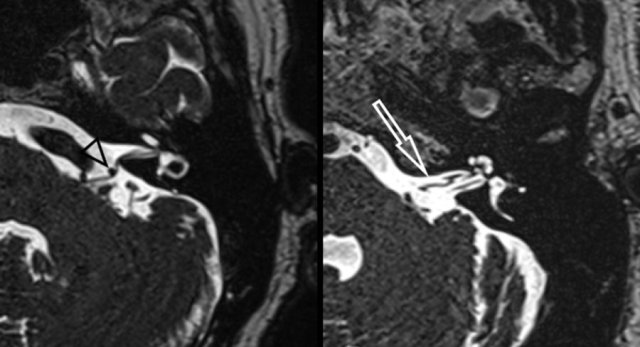

Both CT and MRI can be used for the detection and evaluation of a paraganglioma.

The majority of tympanic paragangliomas are located on the promontory as a small well-defined tympanic soft tissue mass.

Usually, there is no or little surrounding bone erosion.

These small tumours are best evaluated using thin-sliced CT with a bone algorithm.

Left Axial CT shows a soft tissue mass in the middle ear (arrows).

No visible bony erosion.

Right Axial contrast enhanced T1-W with fat suppression demonstrates strong enhancement of this lesion(arrowhead).